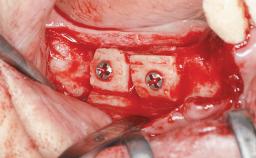

Guided Bone Regeneration (GBR) with a Particulated Autologous Graft and a ePTFE-Reinforced Membrane for Vertical Augmentation of a Single-Tooth Edentulous Space in the Esthetic Zone

A 47-year-old Caucasian woman with a single-tooth edentulous space at the site of the left maxillary canine was referred for treatment. She had undergone traumatic extraction of this impacted canine several months before referral. Her chief complaint was the dissatisfying appearance of her smile. The patient desired a stable and esthetic rehabilitation of the site. Her dental history showed no evidence of periodontal disease or bruxism. She had no systemic diseases, was not taking any medications, and did not smoke. The extraoral examination revealed a high lip line and an inadequate soft-tissue volume at the defective canine site. Large black triangles were visible between the canine and its adjacent teeth.